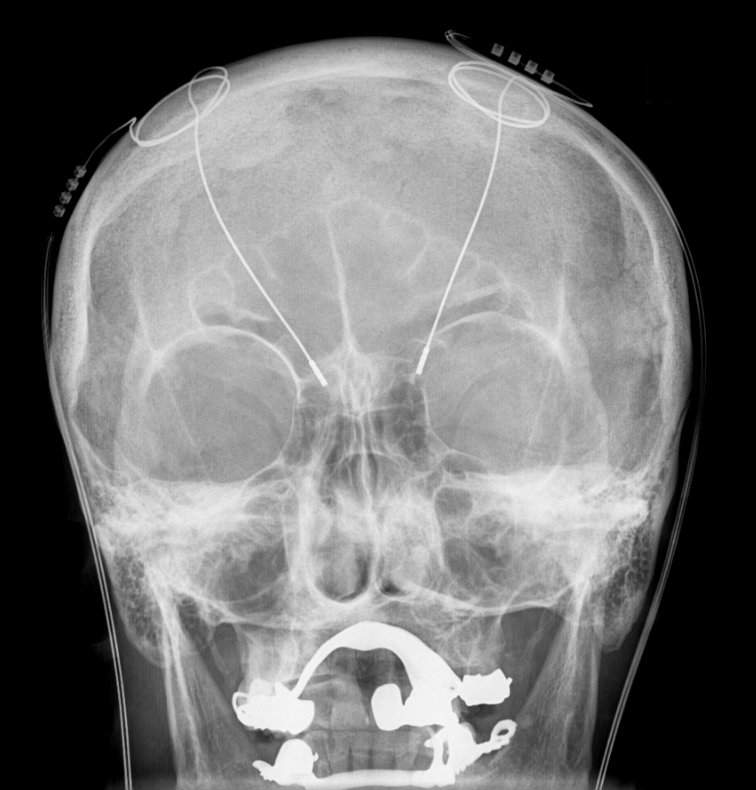

Deep Brain Stimulation (DBS) is a major neurosurgical procedure that’s indicated when medications do not control severe motor symptoms of Parkinson’s Disease. Prior to surgery, image studies are obtained to pin-point the targeted area of the brain, such as the subthalamic nucleus thought to be implicated in PD.

The procedure is initially done while the person is awake and involves placing electrode(s) in the targeted area of the brain. Later under general anesthesia. the electrode is connected to a wire that runs from the head, down the neck and shoulder into the chest region where it is attached to a device called a pulse generator. Some have called this, a “brain pacemaker.”

Once the generator is turned on, it emits electrical signals twenty fours per day that change the brain’s neural activity. In people with PD, the objective is to block the brain’s activity that causes tremors and unwanted movements. As with all surgical procedures, there are risks involved and the procedure doesn’t work for everyone.